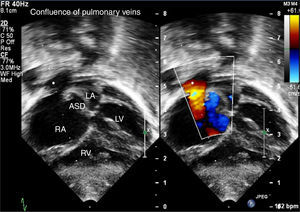

Echocardiography confirmed situs solitus and levocardia. All four pulmonary veins were imaged forming a confluence which opened directly into the right atrium with a mean gradient of 8 mmHg (Figures 1–3). There was no vertical vein and the coronary sinus was normal. Individual pulmonary veins were adequately sized. The ASD was of ostium secundum type, measuring 4.7 mm, with mildly restrictive peak and mean gradients of 5 and 1 mmHg, respectively. Surgical exploration revealed all pulmonary veins draining to the right atrium with a shelf over the opening of the left pulmonary veins. The patient underwent primary sutureless TAPVC repair and closure of the ASD with a tanned pericardial patch, and is doing well.